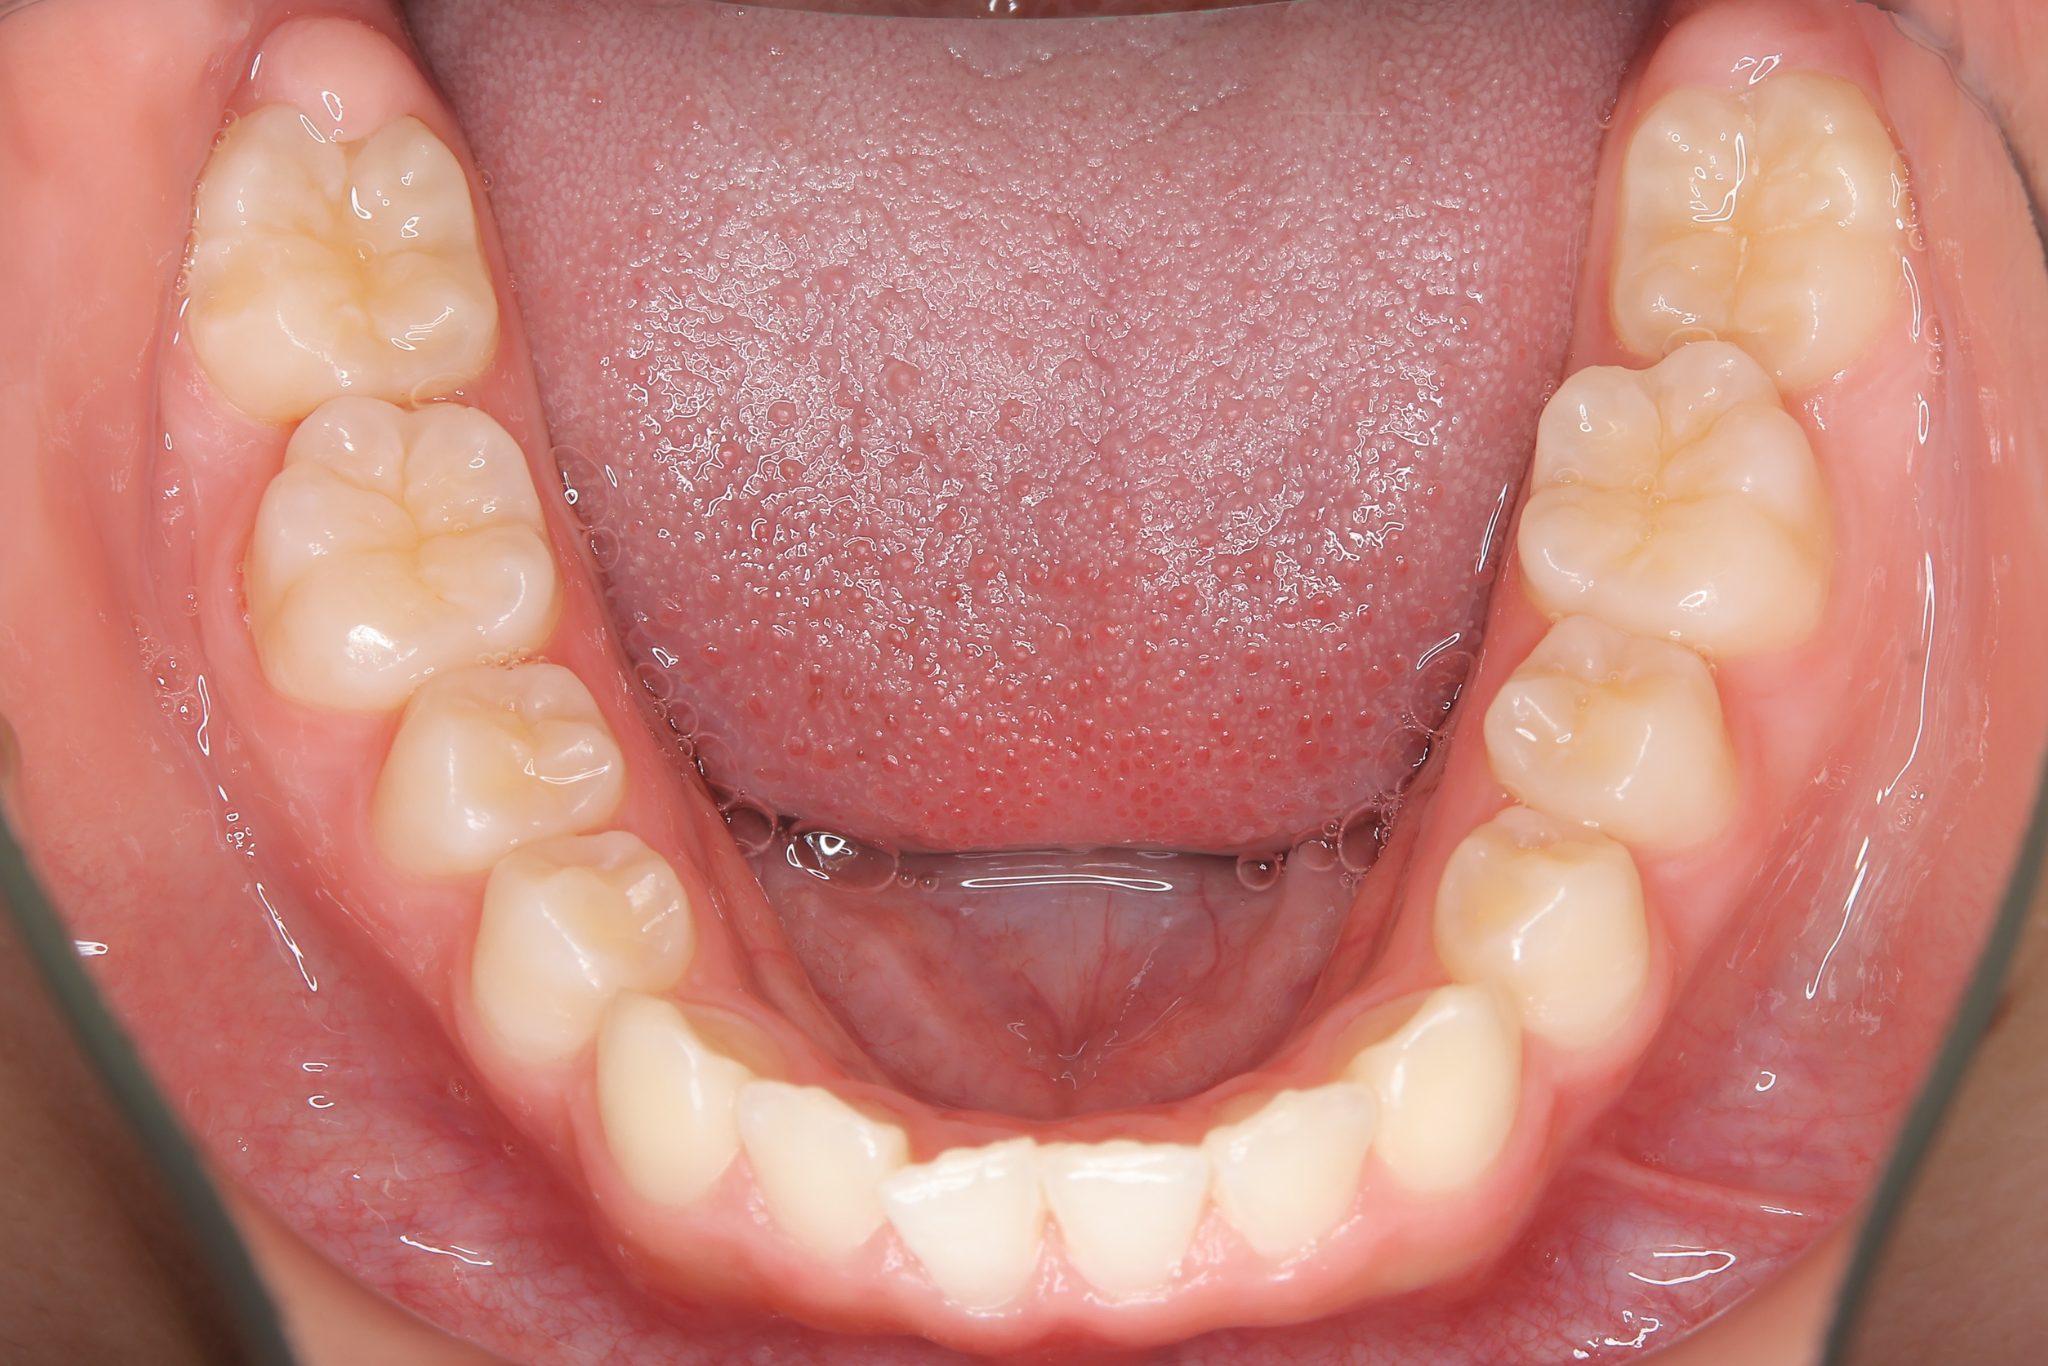

全顎ワイヤー矯正 症例_610 Case

ビフォー

| 主訴 | 前歯の歯並び|歯ぎしり |

| 施術内容 | 小児矯正1期治療 |

| 治癒期間 | 2年4か月間 |

| 費用 | 711,700円(税込) |

| リスク・副作用 | 違和感、不快感、痛み |